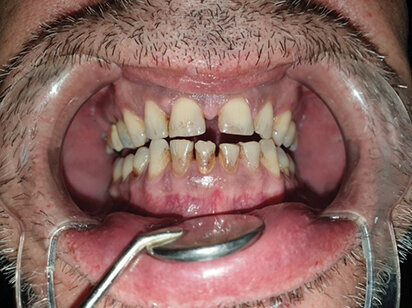

Pacijent B pušač pri prijemu. Estetski neprihvatljive pušačke pigmentacije na svim površinama zuba, naročito onim u estetskoj zoni, direktno izloženim glavnoj struji duvanskog dima. Zubni kamenac i meke naslage ukazuju na nizak nivo oralne higijene. Uočava se i prebojenost kompozitnih aproksimalnih plombi gornjih prednjih zuba. Slabije izražene melanogene pigmentacije desni. Jezik pacijenta takođe je obložen (Sl. 2.0).

Sl. 2.0: Pacijent B, pušač pri prijemu